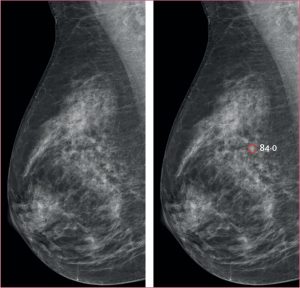

Cercetarea a inclus aproape 106.000 de femei din Suedia, împărțite în două grupuri: unul a fost evaluat prin mamografie standard interpretată de radiologi, iar celălalt a beneficiat de analiza asistată de AI. Rezultatele au fost impresionante – inteligența artificială a identificat 338 de cazuri de cancer, comparativ cu doar 262 în grupul evaluat tradițional. Mai mult, AI a detectat cu 24% mai multe cancere invazive aflate în faze incipiente, ceea ce poate îmbunătăți semnificativ șansele de tratament și supraviețuire.